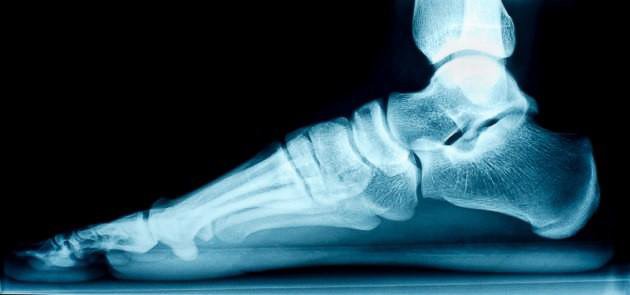

Cuando esto sucede, el Médico Traumatólogo Ortopedista, hace el diagnóstico con pruebas sencillas en el consultorio, analizando la forma de caminar de cada niño, apoyándose en la observación meticulosa del pie con un aparato llamado plantoscopio; también lo hace observando el desgaste del calzado. La solicitud de radiografías las determinará el especialista, sólo en casos de sospecha de alteraciones óseas y, el tratamiento, lo llevará a cabo el Médico con base a las características de cada niño, en el cual están incluidos ejercicios que fortalezcan los músculos del pie; y, en algunos casos, el uso de plantillas, zapatos de tipo ortopédico y raramente la cirugía.